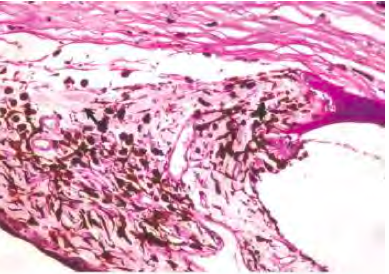

What is the most likely cause of the corneal opacity?

Glaucoma

= ↑ IOP

obstruction of the filtration angle

Goniodysgenesis, primary glaucoma